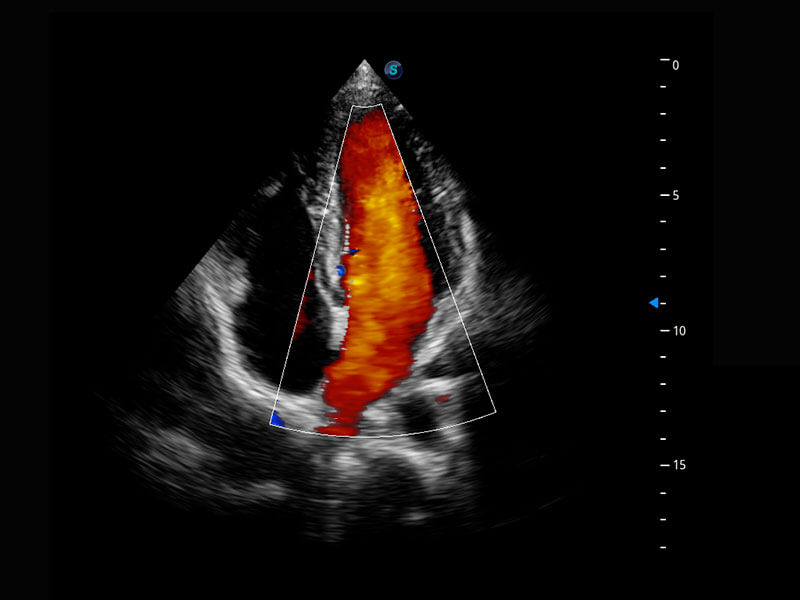

乳腺超声 / 新生儿

P60搭载宽频带线阵探头、宽景成像、弹性成像技术,为您提供乳腺应用方案。P60支持高频相控阵探头、线阵探头、腹部高频探头、腹部微凸探头等,丰富的探头群搭载敏感的彩色血流成像,适用于新生儿多种脏器检测要求,满足新生儿筛查需求。

• 新生儿心脏